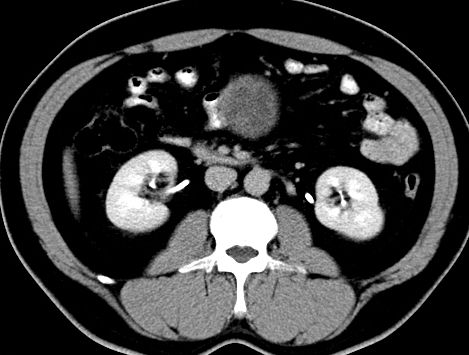

(腹腔)神经鞘瘤

男,48岁,间断性下腹不适1年。

手术探查

:距回盲部28厘米处肠系膜根部可见5*7cm左右包块,质中等硬度,活动度尚可,肝、胆、胰、脾肾未见明显异常。

病理

:(腹腔)

神经鞘瘤

,伴出血、坏死及囊性变,伴淋巴结反应性增生。

免疫组化结果

:sma(-), desmin(-), cd117(-), s-100(+++), nf(-),vimentin(+++).